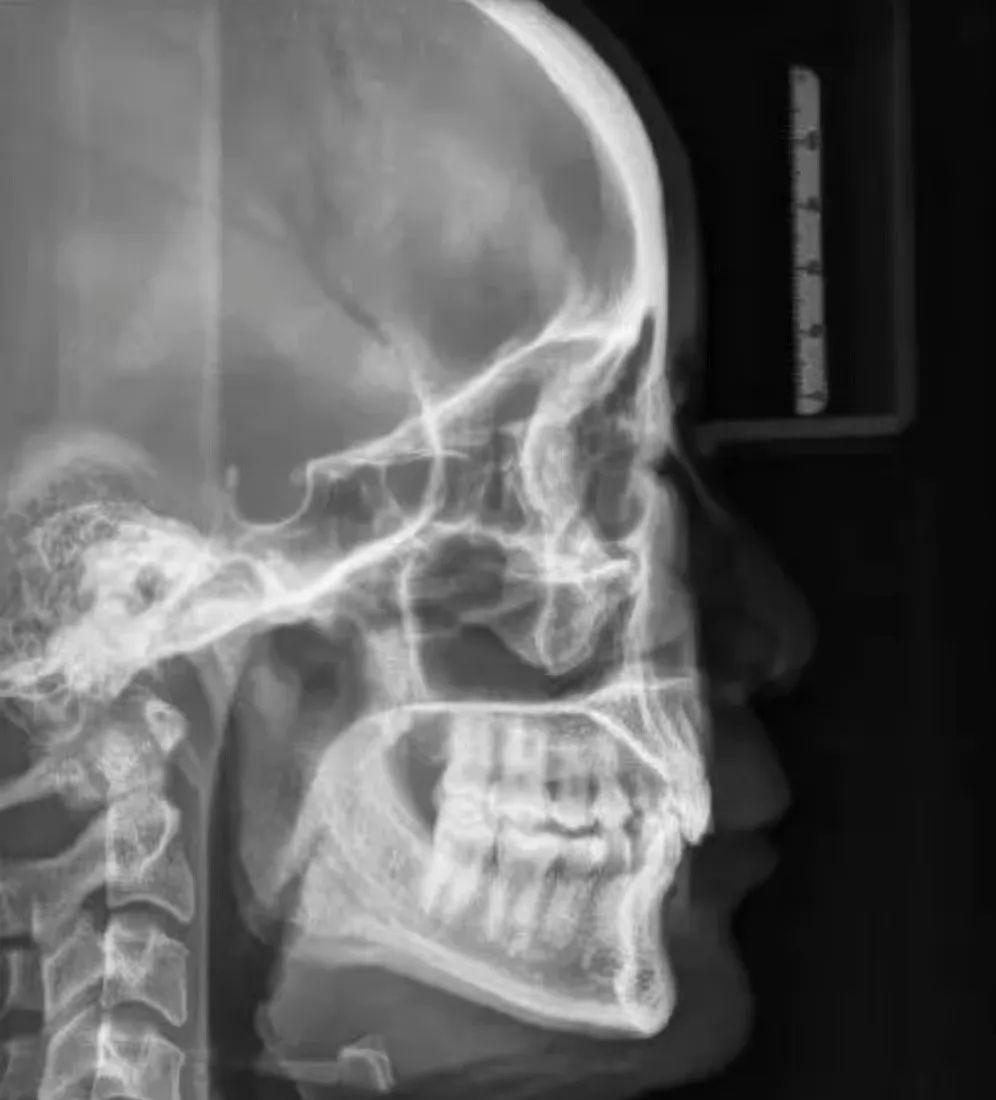

其基本原理是X线发生器以较低的射线量(通常球管电流在10毫安左右)围绕投照体做环形数字式投照,然后将围绕投照体多次数字投照后“交集”中所获得的数据在计算机中“重组”,进而获得高清三维图像。卡瓦X-TREND“三合一”CBCT即具有口腔曲面断层片、头颅侧位定位片和多功能CT三种拍摄功能,满足了口腔临床诊断的所有需要。

4、牙列错颌畸形矫治方面:用于研究颅面生长发育,诊断分析、矫治设计、前后对比,头影测量等。